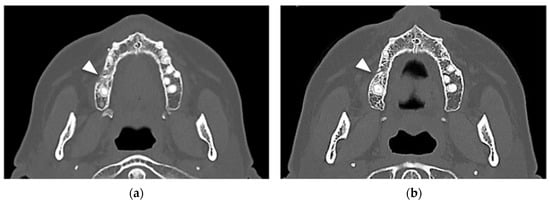

At computed tomography (CT), cortical erosion and widening of the periodontal space were detected. A focal increased trabecular bone density with loss of trabecular architecture was also detected around the alveolar bone. The radiological bone changes mainly involved the area of the first right molar but also extended to the alveolar bone of the second molar. The thickening of the maxillary sinus membrane was suggestive of a process involving the entire bone height (Figure 3a,b).

Figure 3. (a) Coronal CT view showing a cortical vestibular interruption at the site of the first right molar with an irregular trabecular pattern of alveolar bone (white arrowhead); (b) Axial CT view: a focal medullar bone sclerosis entirely surrounded the first molar roots with an extension at the area of the second molar associated with a thickening of the lamina dura (white arrowhead).